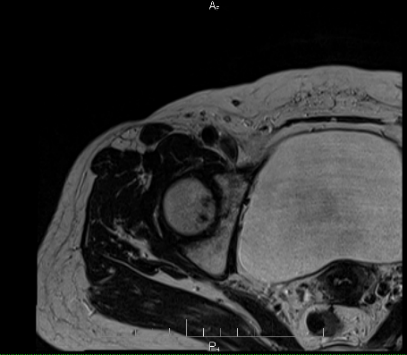

Sau khi chụp MRI kết quả cho thấy tổn thương vùng chỏm xương đùi phải với vùng giảm tín hiệu trên T1,T2, tăng tín hiệu trên STIR, những tổn thương sớm này không thể quan sát thấy được trên chụp Xquang thường quy.

Hình ảnh Xquang và MRI của bệnh nhân

Bệnh nhân được chẩn đoán hoại tử chỏm xương đùi phải giai đoạn II theo phân loại Arlet – Ficat. Với những tổn thương phát hiện sớm như thế này, bệnh nhân sẽ được điều trị nội khoa nhằm bảo tồn khớp háng.